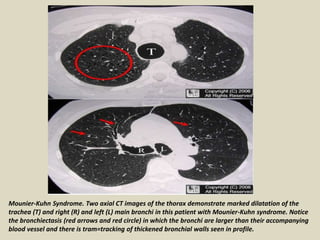

Mounier-Kuhn Syndrome. Two axial CT images of the thorax demonstrate marked dilatation of the

trachea (T) and right (R) and left (L) main bronchi in this patient with Mounier-Kuhn syndrome. Notice

the bronchiectasis (red arrows and red circle) in which the bronchi are larger than their accompanying

blood vessel and there is tram=tracking of thickened bronchial walls seen in profile.